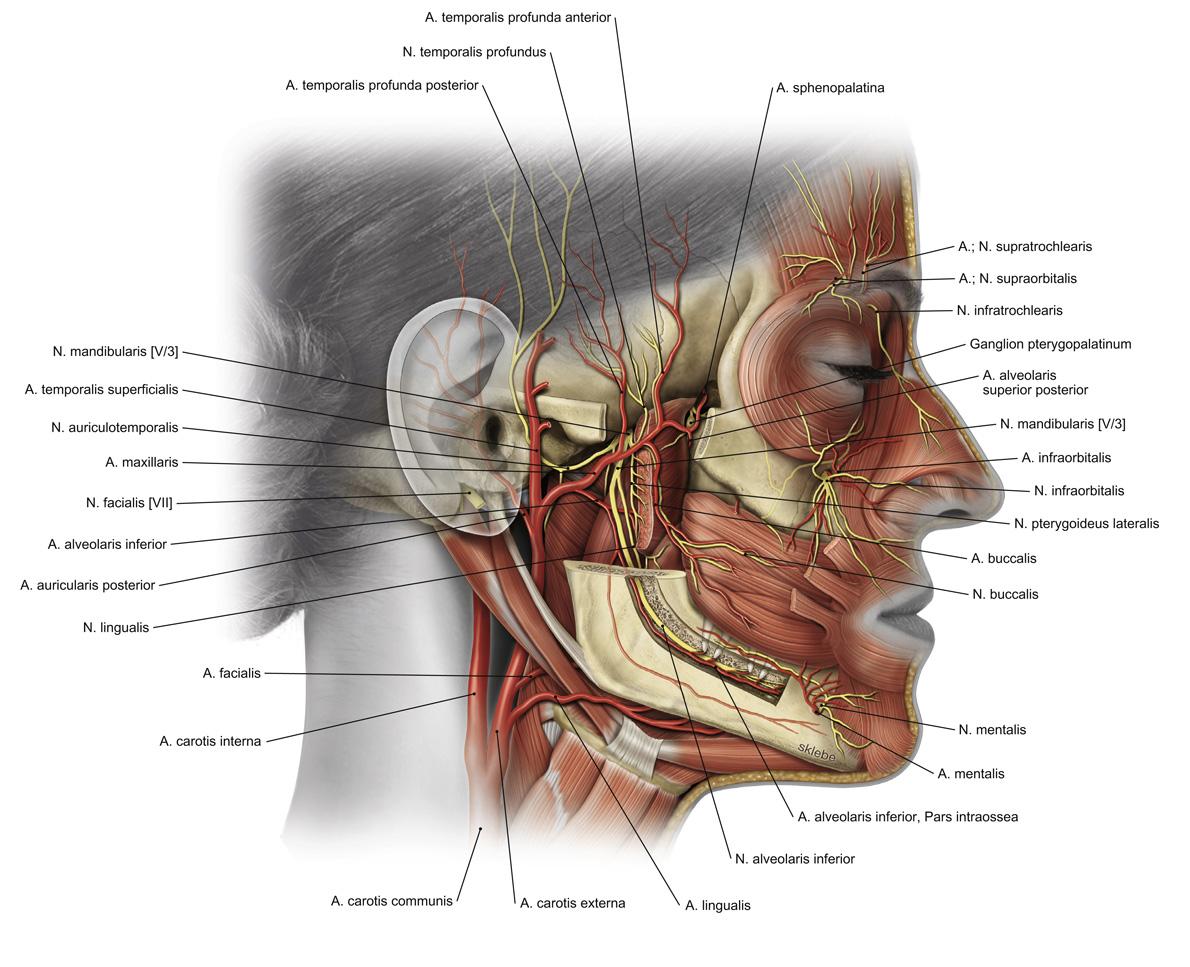

Fig 3.08: a. carotis externa - eindtakken

proc. mastoideus meatus acusticus externus arcus zygomaticum = zygoma collum mandibulae glandula parotis a maxillaris (langs m. pterygoideus naar fossa pterygopalatina) -

a temporalis superficialis

onder glandula parotis r frontalis r parietalis

Fig 3.09a: a. maxillaris - takken van het kaakdeel en spierig deel

A kaakdeel (oranje)

(a auricularis profunda) (a tympanica anterior) -

a alveolaris inferior

-

a meningea media

B spierig deel (groen)